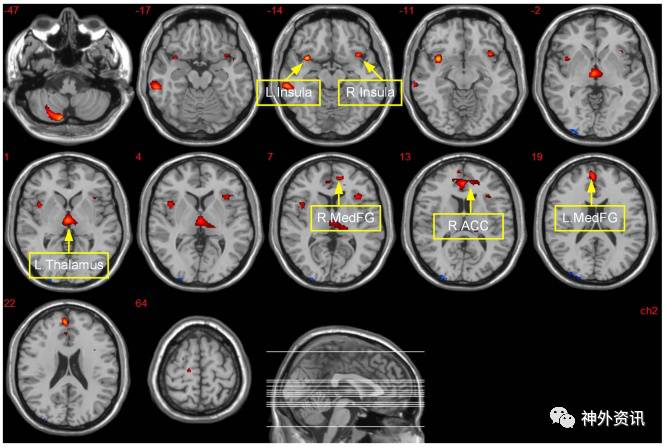

结果显示,与正常体质指数人群组相比,肥胖组患者在额区与边缘区的灰质体积均减少(图1)。正常组中发现,前扣带回皮质体积与缺乏毅力和恒心呈负相关(R=−0.372,p=0.009),岛叶的灰质体积与缺乏紧迫感呈负相关(R=−0.364,p=0.010)。肥胖组中,左侧杏仁核与右侧苍白球的灰质体积与寻求感觉呈负相关(前者R=−0.414,p=0.010;后者R=−0.448,p=0.010)。

图1. 肥胖组与正常体质指数组患者大脑灰质特定区域体积改变具有统计学意义(p=0.005);红色区域代表肥胖组比正常组灰质体积明显减少的部位,蓝色区域代表肥胖组比正常组灰质体积增加的部位。R. MedFG:右额内侧回;R. ACC:右侧前扣带皮质;L. MedFG:左额内侧回。